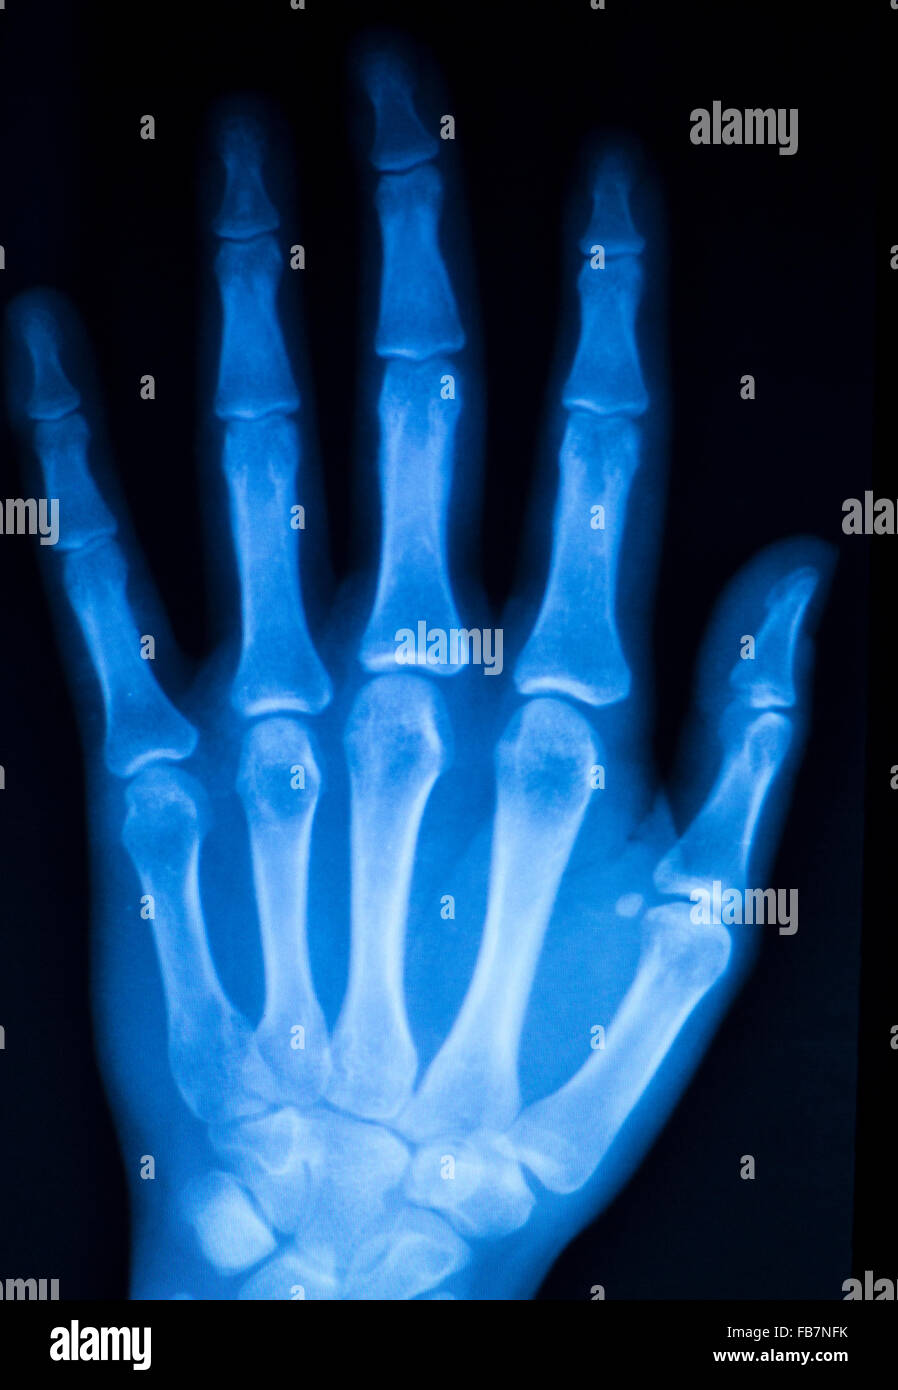

From www.alamy.com

Hand, fingers and thumb hospital xray scan test results for joint pain Finger Joint Pain No Injury There are different reasons why. Fingers are able to perform incredible and intricate work. It’s often caused by an accident or a medical. Your symptoms might also give. finger pain is a throbbing, cramplike, or achy pain that’s felt in any of your fingers or your thumb. Here are 27 causes to consider and how they are treated. The. Finger Joint Pain No Injury.